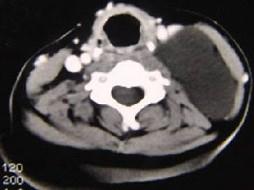

问题 男性,40岁,颈部出现无痛性囊性包块2年余,CT扫描如图所示,最可能诊断为 ( )

选项 A、神经源性肿瘤 B、颈动脉鞘瘤 C、血管瘤 D、淋巴结肿大 E、淋巴管瘤

答案 E